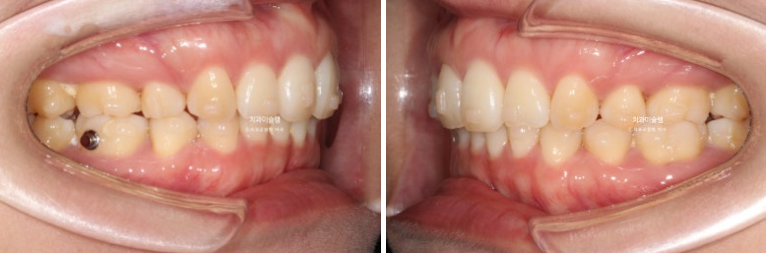

26.01

이제 전후 비교 보겠습니다.

총 치료기간은 3년 2개월, 재제작은 3회 했습니다.

어금니 교합은 뜨는 곳 없이 좋습니다.

앞니 각도는 적절하며

아래 앞니는 계획대로 뒤로 1mm도 뒤로 들어감 없이 잘 유지가 되었고 위 앞니는 치조골이 허용하는 범위 내에서 아래앞니와 만나기 위해 최대한 뒤로 들어갔습니다.